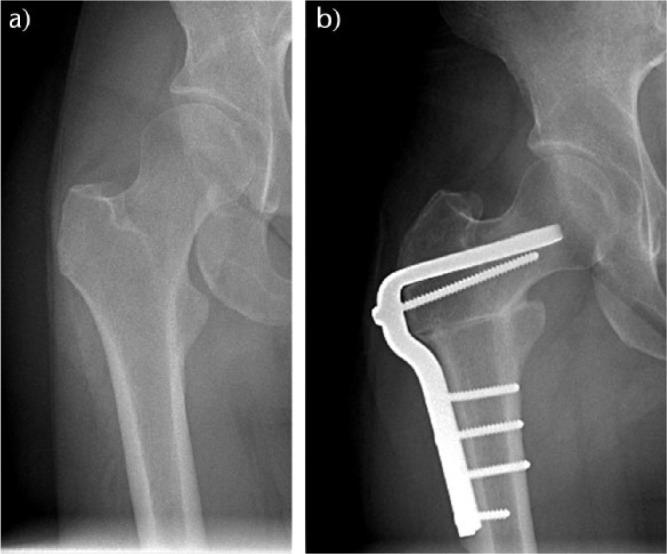

In this review, we bring to the attention of the reader three relatively unknown types of hip impingement. We explain the concept of low anterior inferior iliac spine (AIIS) impingement, also known as sub-spine impingement, ischio-femoral impingement (IFI) and pelvi-trochanteric impingement. For each type of impingement, we performed a search of relevant literature.We searched the PubMed, Medline (Ovid) and Embase databases from 1960 to March 2016. For each different type of impingement, a different search strategy was conducted.In total, 19 studies were included and described. No data analysis was performed since there was not much comparable data between studies.An overview of symptoms, clinical tests and possible surgical treatment options for the three different types of extra-articular impingement is provided.Several disorders around the hip can cause similar complaints. Therefore, we plead for a standardized classification. In young and athletic patients, in particular, there is much to gain if hip impingement is diagnosed early. Cite this article: 2018;3:30-38. DOI: 10.1302/2058-5241.3.160068.